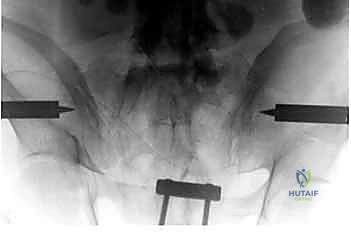

الخطوة الرابعة: تركيب الإطار الخارجي (The Frame)

بمجرد تثبيت المسامير بقوة في العظام، يتم توصيل الأجزاء الخارجية منها بأعمدة (قضبان) مصنوعة من ألياف الكربون (Carbon fiber) أو المعادن الخفيفة باستخدام مشابك قابلة للتعديل.

الخطوة الخامسة: الرد (Reduction) والتثبيت النهائي

يقوم الدكتور هطيف يدوياً بالضغط على الحوض لإغلاق "الكتاب المفتوح" (رد الكسر إلى وضعه الطبيعي التشريحي). بمجرد تحقيق الوضع الأمثل والتأكد منه عبر جهاز الأشعة، يتم إحكام ربط المشابك لتثبيت الإطار الخارجي بشكل صلب ونهائي، مما يمنع أي حركة إضافية للحوض ويوقف النزيف فوراً.